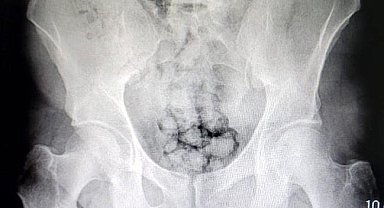

Uyuşturucuları midelerine sakladılar, polis tarafından kıskıvrak yakalandılar